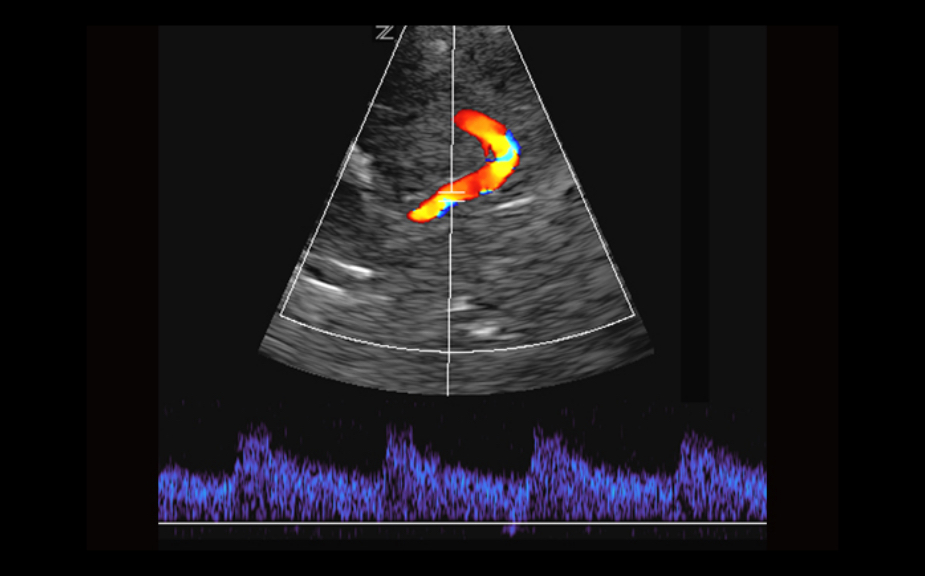

Equipado con software patentado con base en tecnolog├Ła ZONE?Sonography? (ZST),?el Z.One PRO proporciona toma de im├Īgenes Doppler y Modo-B detalladas ├│ptimamente para pacientes, sin importar la complexi├│n del cuerpo, ayudando a asegurar un diagn├│stico confiable.

A trav├®s de una amplia gama de aplicaciones, el Z.One PRO es la soluci├│n de ultrasonido para sus exigentes desaf├Łos cl├Łnicos.

- Insuperable calidad de imagen en todas las aplicaciones

- Doppler CW con transductores auxiliares